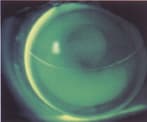

Figure 1. Posterior aspheric GP lens with superior positioning and central

alignment. |

The three basic GP simultaneous designs are concentric annular or target, de Carle and aspheric. The first two are non-aspheric and have no prism ballast for orientation. Aspheric designs can have single or multiple posterior aspheric curves with a spherical front surface, or a single posterior aspheric curve with an aspheric anterior surface. These designs offer options for individual advantages (Figure 1).